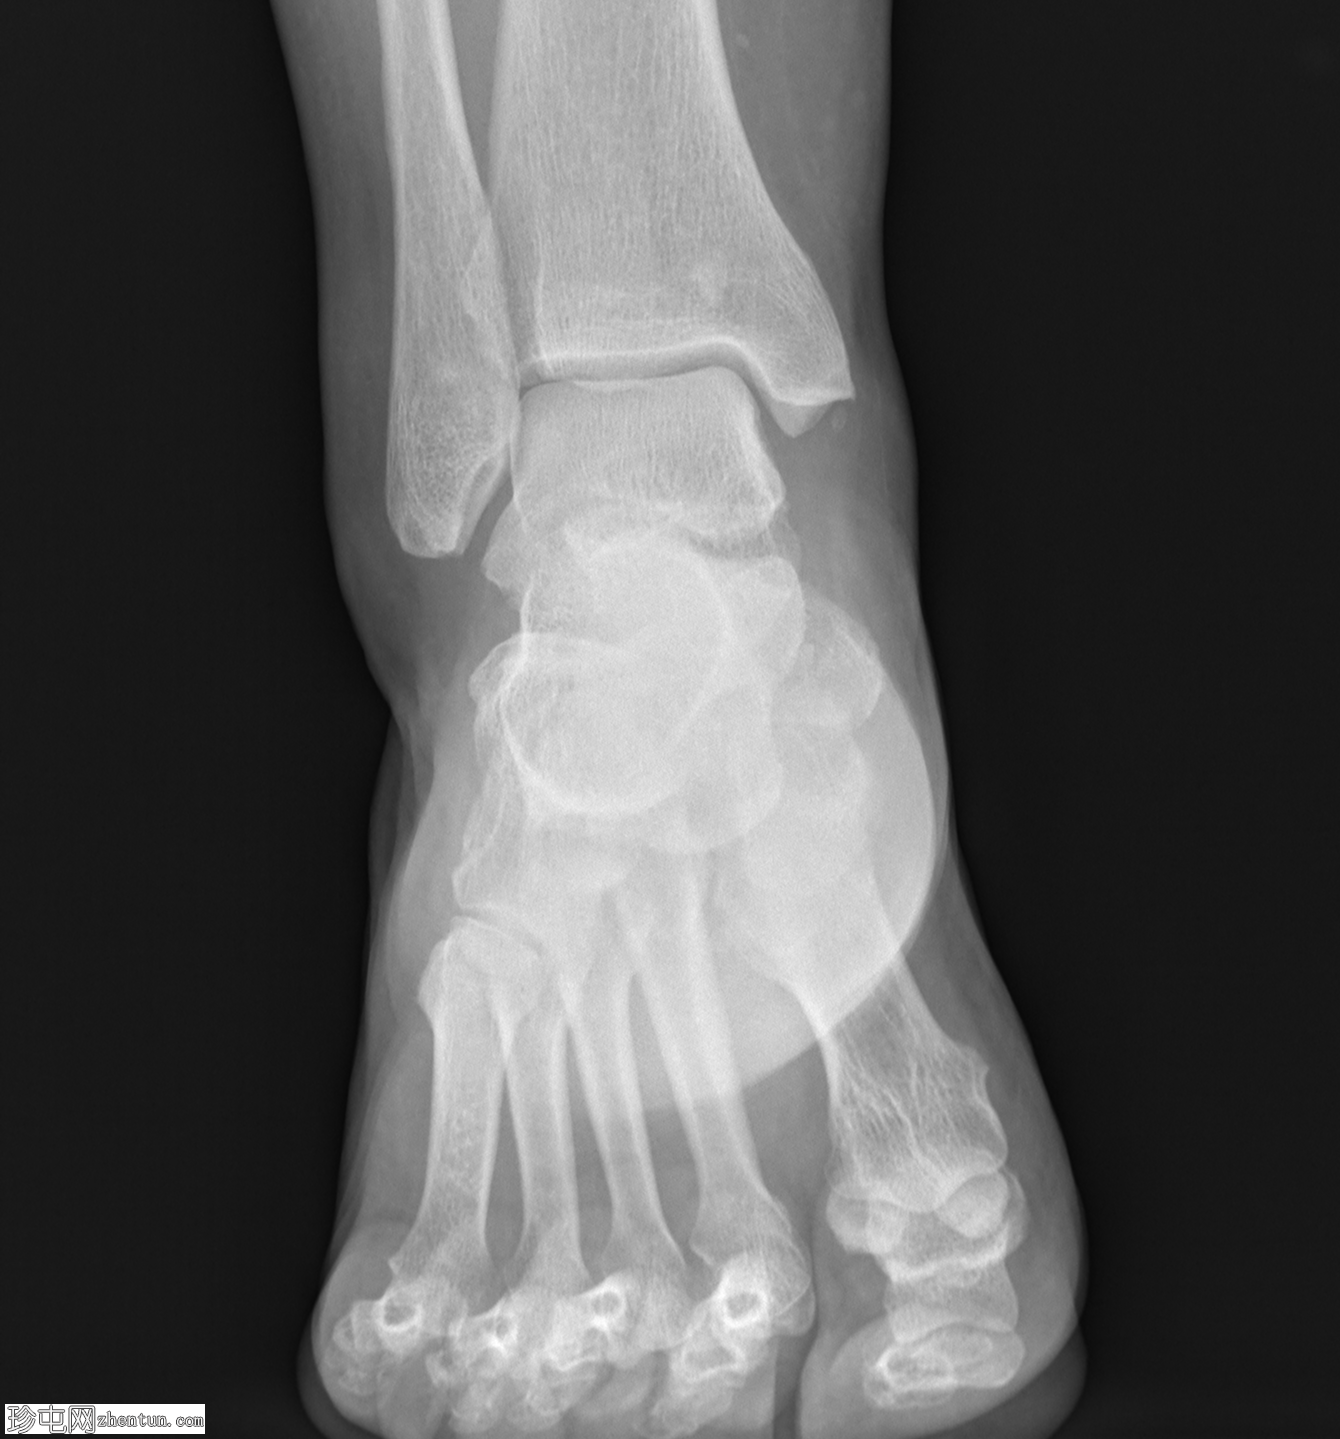

X光片

侧位

正位

沿足底筋膜走行可见两处相邻的小钙化灶。跟腱附着点病和足底跟腱骨赘形成。腓籽骨副骨。

一名中年女性,既往有软组织损伤史,出现足底筋膜钙化。